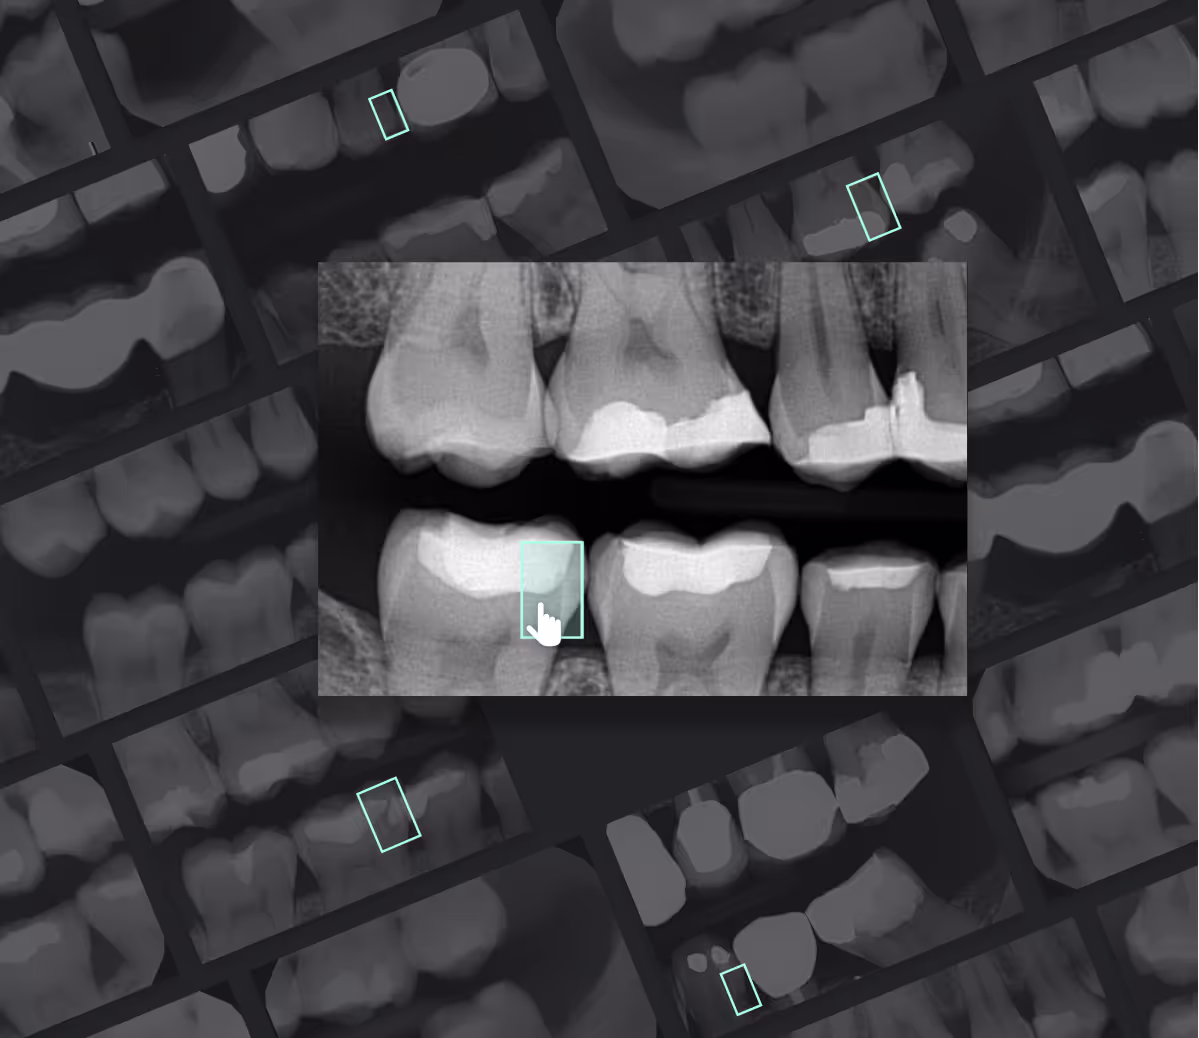

Real Cases

What our clinical team finds

✓ Confirmed

Crown β€” Tooth #5

Patient presented with a $1,400 crown recommendation. Our team confirmed structural compromise from an existing large filling. Treatment was appropriate and necessary.

$1,400 treatment confirmed β€” proceed with confidence

Modified

Bridge + Implant Plan

$6,800 combined bridge and implant treatment plan. Review identified bridge as premature given remaining bone health. Patient deferred the bridge, proceeding only with the implant.

$2,100 saved by deferring premature procedure

Price Concern

Periodontal Treatment

Deep cleaning (SRP) recommended at $1,200/quadrant β€” well above market rates. Patient was guided to a KELLS network provider offering the same treatment at $380/quadrant.

$3,280 saved through network repricing